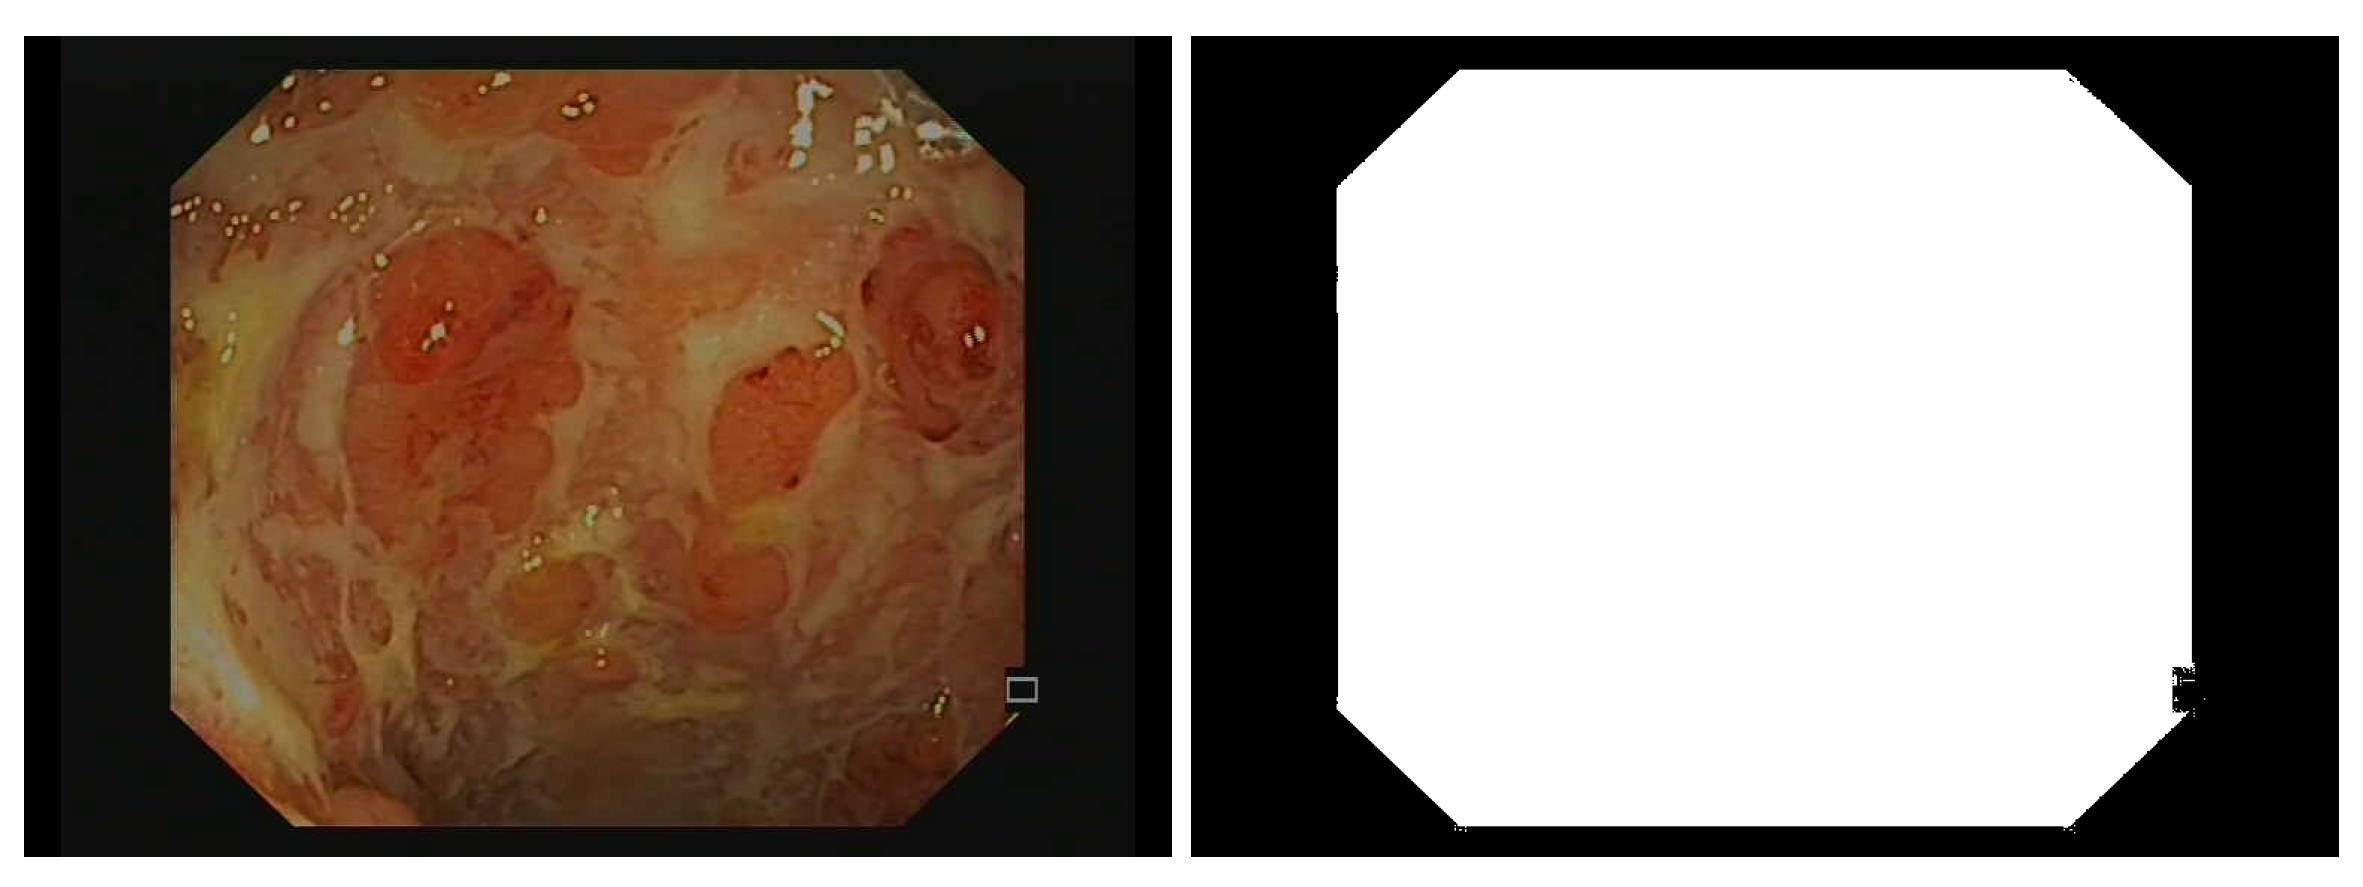

- -

3.2.1. Image Preprocessing